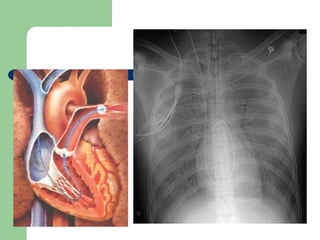

 Rx de tórax AP simples

Choque  MONITORIZAÇÃO  Oximetria Gasometria Arterial  Bioquímicos: U, C, Na, K  Rx de tórax AP simples  HEMODINÂMICA